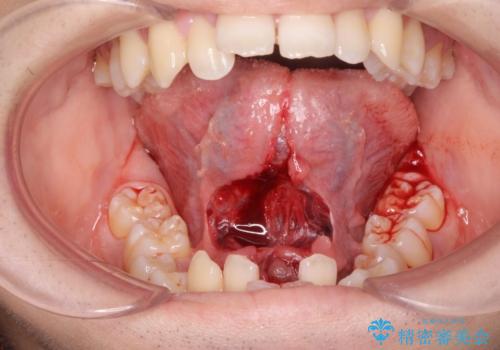

- 滑舌が悪いとの事で来院。

当日に舌小帯の切除を行う事になりました。

手術は当日に行う事ができ、一週間後に抜糸を行います。